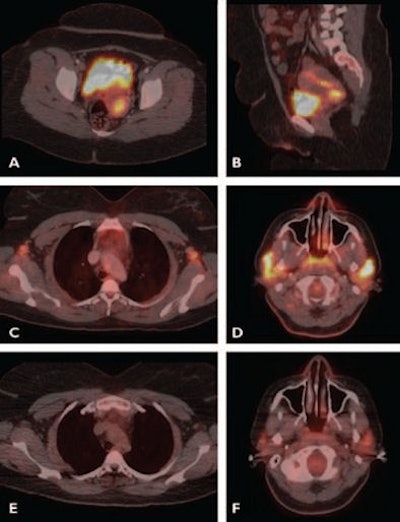

| Images are of a 31-year-old woman with HIV who was evaluated for initial staging of biopsy-proven stage IIIB squamous cell carcinoma of the cervix. Axial (A) and sagittal (B) fused PET/CT images show F-18 FDG uptake in cervix with maximum standardized uptake value of 8.3, consistent with patient’s known malignancy, along with increased FDG uptake in bilateral axillary lymph nodes (C) and markedly increased FDG uptake bilaterally in parotids (D) due to reactive changes from HIV. Postchemotherapy FDG-PET/CT scans show no uptake in bilateral axillary lymph nodes (E) and markedly less activity in parotids (F), consistent with benign uptake. Images courtesy of the American Journal of Roentgenology. |